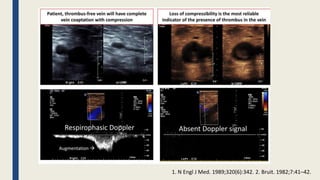

Ultrasound Interpretation ‐ DVT

■ DUS is the test of choice for diagnosis of proximal DVT

• Sensitivity >95%, Specificity >95%

■ Diagnostic components :Visualization, compressibility, flow, and augmentation

•Transducer compression maneuvers

• Doppler evaluation (color and spectral Doppler waveform analysis)

• Augmentation maneuvers

■ Acute DVT

• Loss of compression

• Dilated vein (diameter > artery)

• Intraluminal echoes from thrombus

• Abnormal/absent color Doppler

• Abnormal/absent PW spectral

Cronenwett, J. L. and K.W. Johnston (2014).””vascular laboratory” Rutherford'sVascular Surgery 8th edition , Chapter 17-18

1. N Engl J Med. 1989;320(6):342. 2. Bruit. 1982;7:41–42.